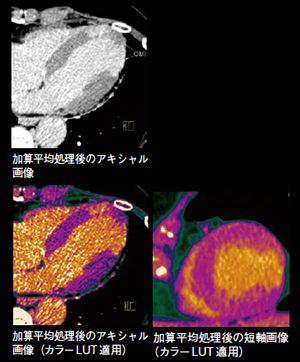

画像加算平均処理を用いた遅延造影CTによる心筋梗塞の描出

【背 景】61歳,女性。1か月前より胸部症状があり,異型狭心症疑いにて心臓CTがオーダされ,冠動脈CTや心筋パーフュージョンを撮影した際に心筋遅延造影CTが施行された。

【所 見】心筋遅延造影CTでは,心尖部(セグメント#14,15,16,17)にほぼ貫壁性の遅延造影が認められた。側壁(#16)には菲薄化が認められた。

【訴求ポイント】心筋梗塞検出のための遅延造影CTは一般的にコントラストが低く,梗塞巣の評価が難しいことがある。また,心電同期によるハーフ再構成特有のアーチファクトにより,心筋の評価が難しいことがある。そこで今回,心筋パーフュージョンと冠動脈CTAで使用した体内に残っている造影剤を利用し,画像加算平均処理を用いた遅延造影を撮影した。SNRを高めるため連続4回撮影し,non-rigidの位置合わせ(ズレの補正)も含めた画像加算平均処理を行った。この処理はコンソール上のVPCTソフトウェアを用いるため,簡便かつルーチンに行うことが可能である。撮影にはコントラストを高め,被ばくを抑えるため低管電圧(80kV)を使用し,さらに心電同期によるハーフ再構成特有のアーチファクトを防ぐため,再構成関数はB23(targeted spatial frequency filtration)を選択した。